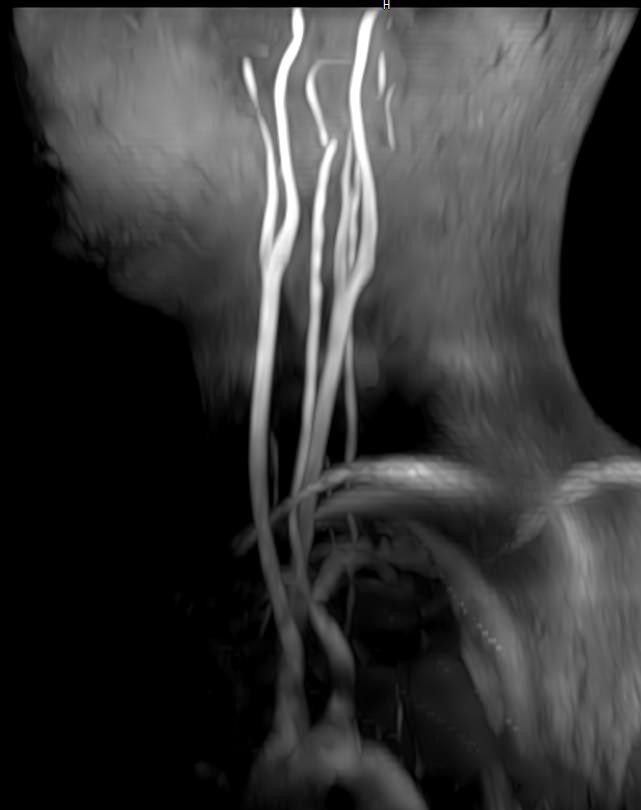

МР-артериография — неинвазивный безопасный метод исследования для диагностики патологии артериальной системы головного мозга. Магнитно-резонансная артериография позволяет получить трехмерное изображение сосудистой системы, кровоснабжающей центральную нервную систему, оценить анатомическое строение артерий головного мозга и функциональные особенности кровотока.

С помощью электромагнитных волн томограф послойно сканирует структуры исследуемого органа, затем посредством компьютерных программ преобразует полученные данные в трехмерное изображение. При этом на снимке видна только сосудистая система без окружающих тканей. Таким образом, сканирование в режиме ангиографии позволяет визуализировать артерии и вены головного мозга без контрастирования.